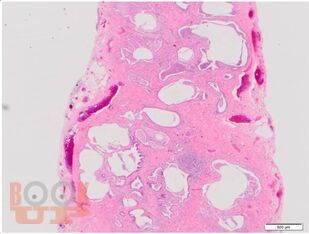

В учебном пособии рассматриваются актуальные и современные вопросы диагностики и лечения интерстициальных заболеваний легких.